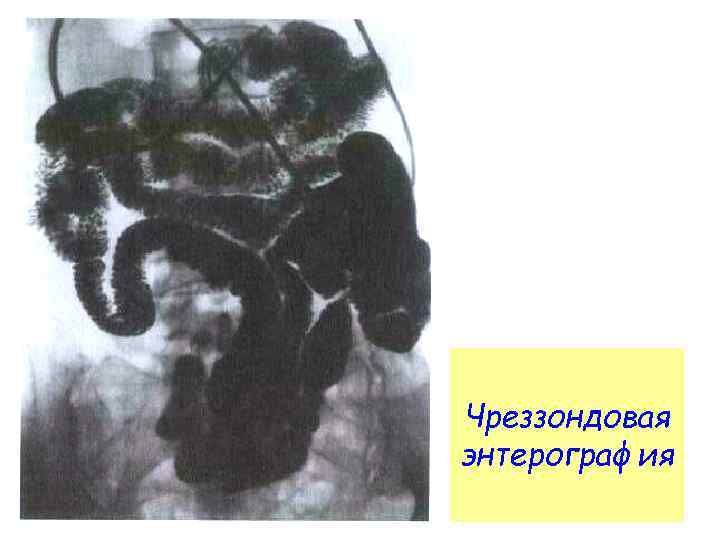

Чреззондовая энтерография